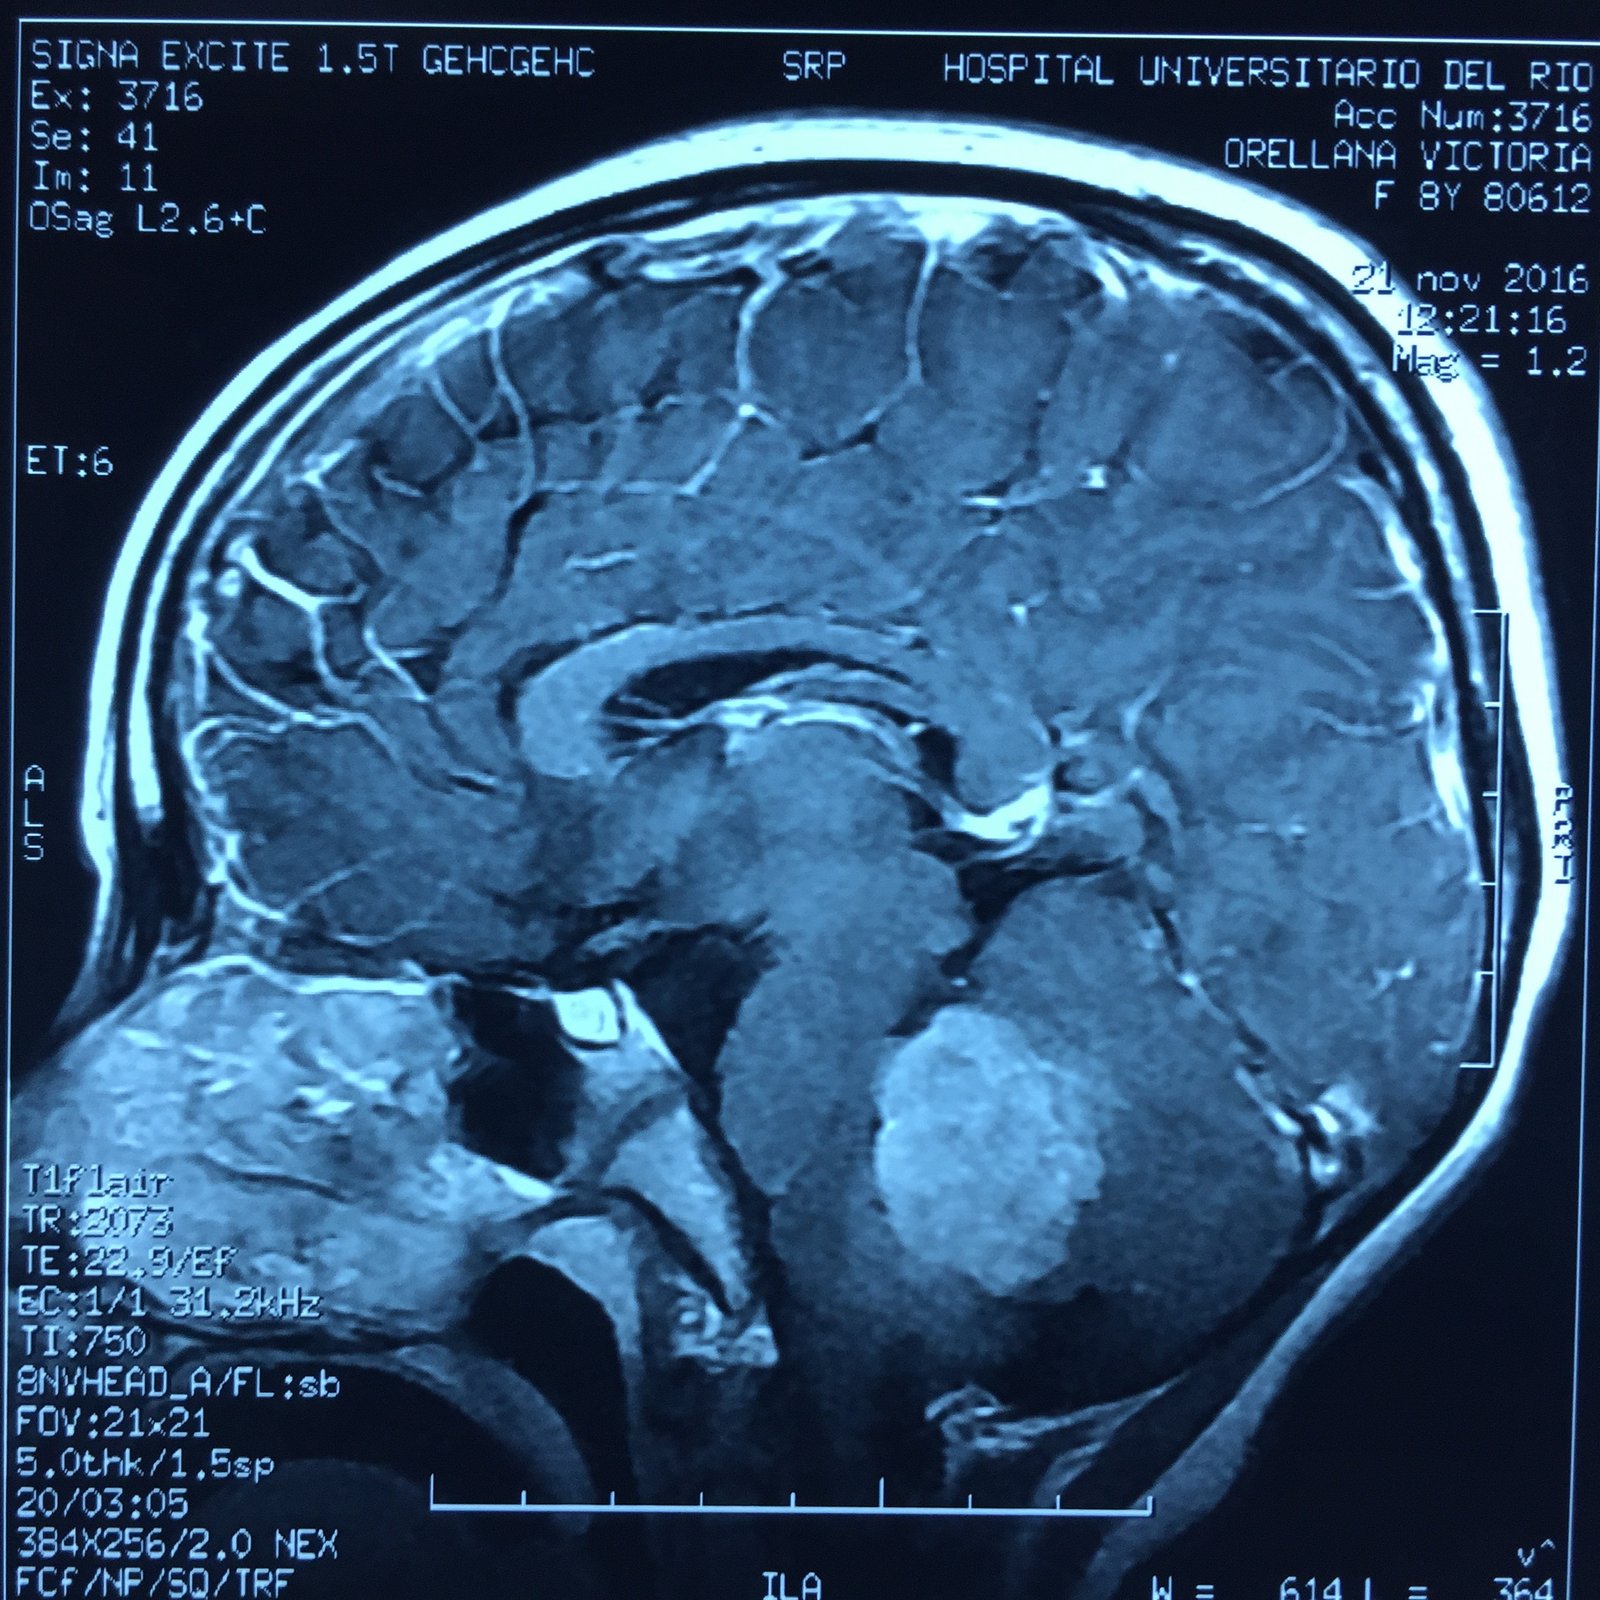

MEDULOBLASTOMA

DESCRIPCIÓN